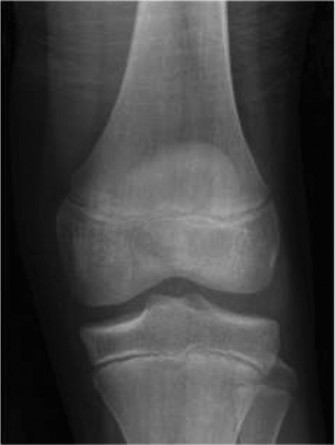

Standard orthogonal radiographs (anteroposterior and lateral views) of the right femur and knee were obtained. The radiographic findings were stark and immediately concerning for a primary malignant bone tumor.

The images revealed a highly aggressive, permeative osteolytic and osteoblastic lesion centered within the intramedullary cavity of the distal femoral metaphysis. The lesion extended through the anterior and medial cortices, demonstrating frank cortical destruction. A florid, aggressive periosteal reaction was evident, characterized by a classic "sunburst" appearance and the presence of a Codman triangle at the proximal margin of the periosteal elevation. These radiographic features represent the rapid, disorganized intramembranous ossification occurring as the tumor outpaces the periosteum's ability to lay down mature bone. Furthermore, a distinct, mineralized soft tissue mass was visible extending anteriorly into the vastus intermedius.